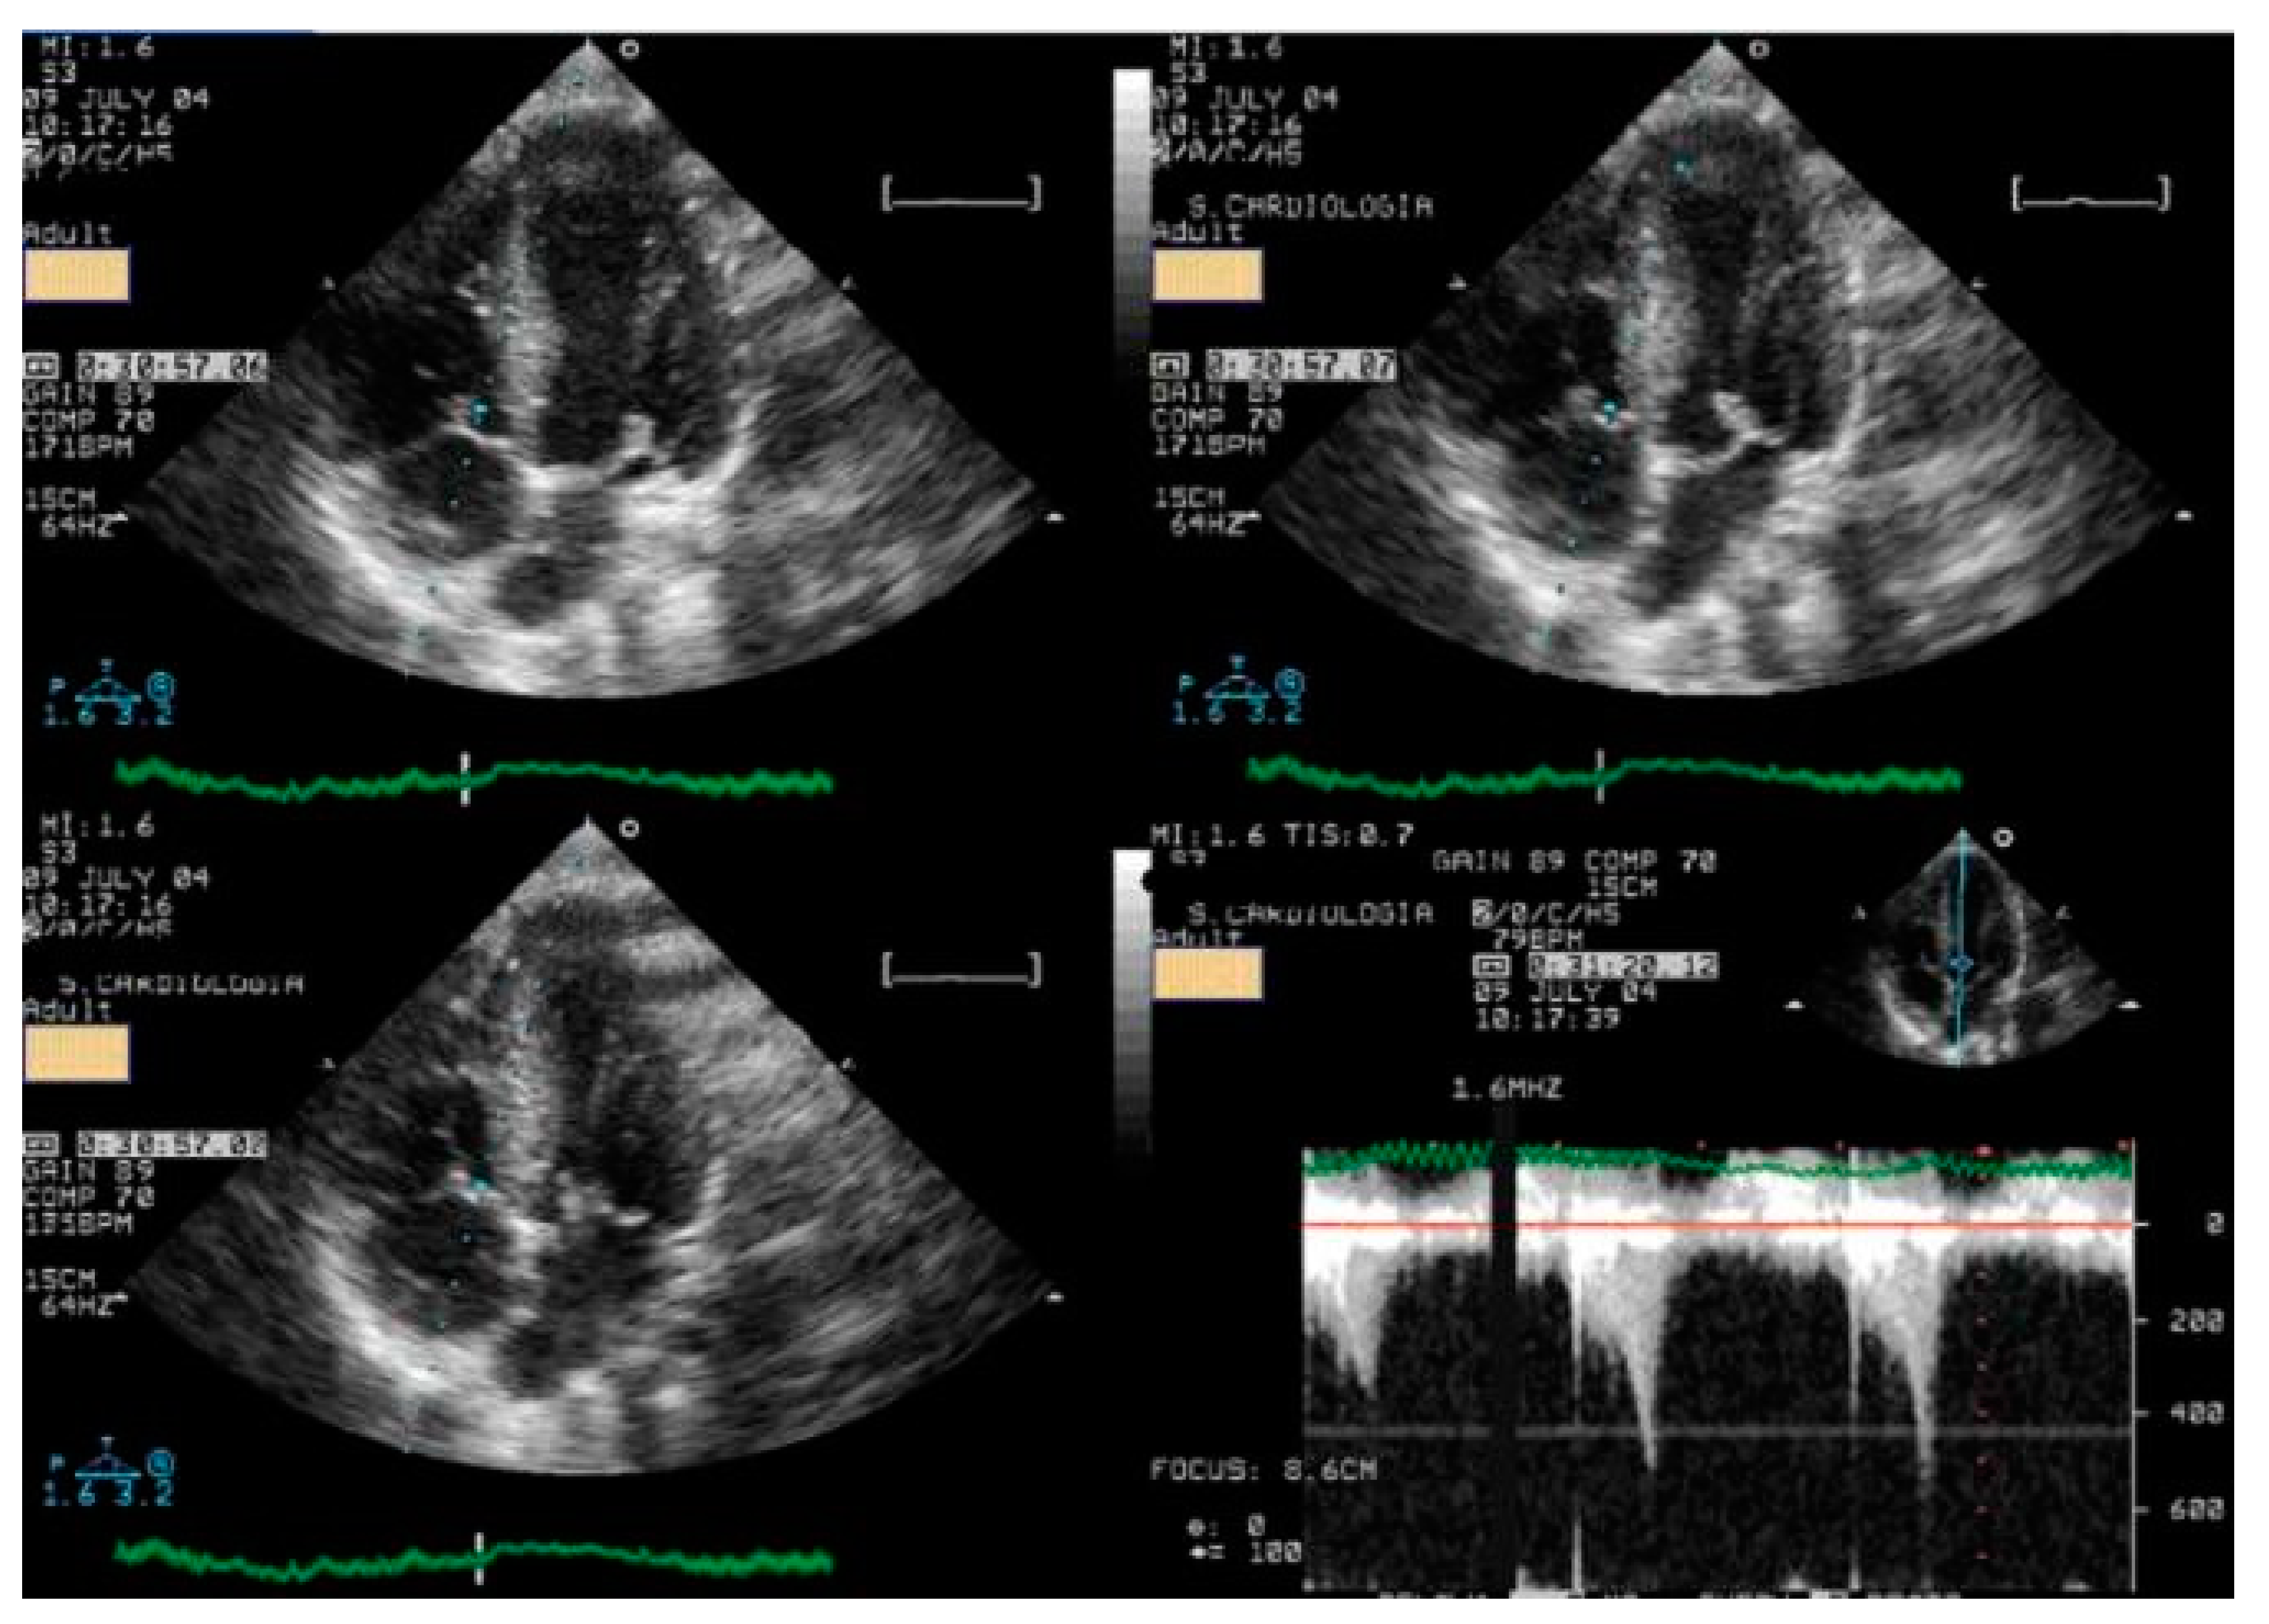

- Lopes, A.; Cotrim, C.; Martins, J.D.; Pinto, F. Exercise-induced intraventricular obstruction in a child with near syncope and chest pain during exercise. Pediatr. Cardiol. 2011, 32, 1032–1035. [Google Scholar] [CrossRef]

- Cotrim, N.; Café, H.M.; Guardado, J.; Cordeiro, P.; Cotrim, H.; Martins, R.; Baquero, L.; Cotrim, C. Clinical Application of Exercise Stress Echocardiography in an Outpatient Pediatric Population. J. Clin. Med. 2024, 13, 2191. [Google Scholar] [CrossRef] [PubMed]

- Cotrim, C.; Almeida, A.G.; Carrageta, M. Clinical significance of intraventricular gradient during effort in an adolescent karate player. Cardiovasc. Ultrasound. 2007, 5, 39. [Google Scholar] [CrossRef]